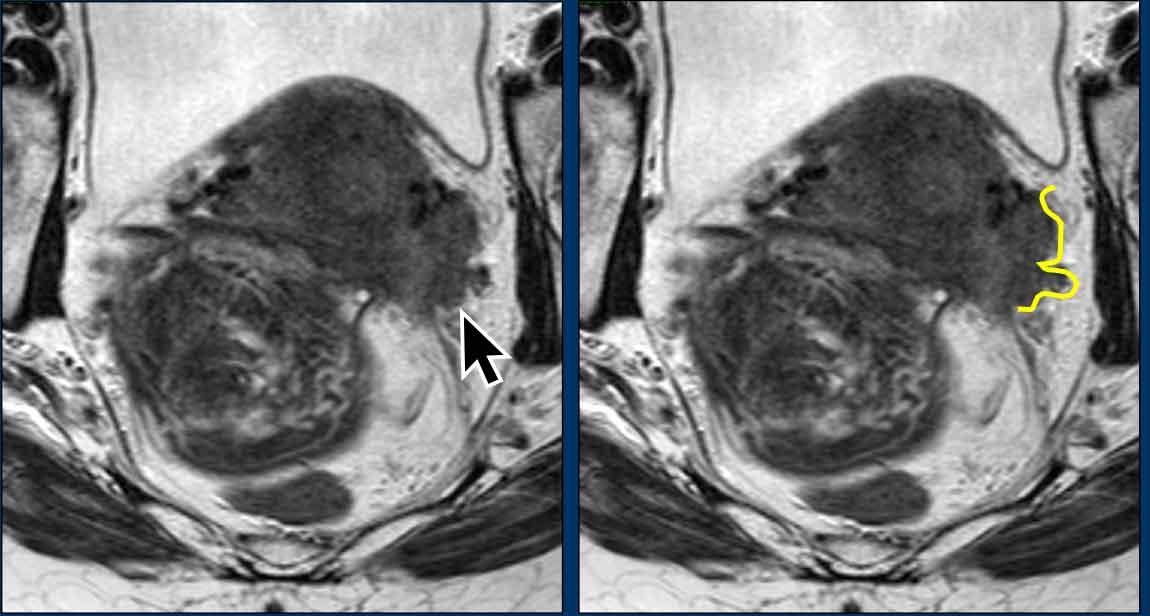

Xâm lấn dây chằng tử cung-cùng

Hình MRI mặt phẳng đứng dọc này cho thấy ung thư cổ tử cung tiến triển tại chỗ (vòng tròn) với xâm lấn lan rộng dọc theo các dây chằng tử cung-cùng (mũi tên).